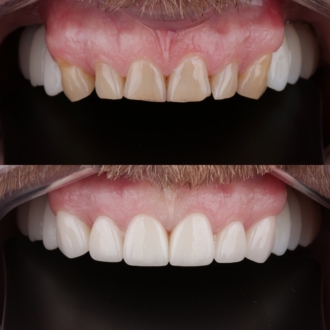

Произведено: диагностику, цифровую планировку улыбки, моделирование формы зубов, минимально инвазивную подготовку, установку керамических реставраций E-max. Результат: гармоничная форма зубов, естественный цвет и прозрачность, правильная длина резцов, более открытая и выразительная улыбка с сохранением собственных тканей зуба.